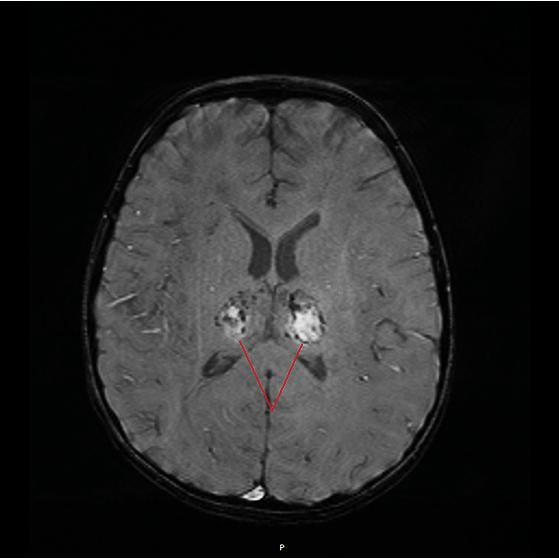

没多久,悦悦的小身板就插满了管子。核磁共振检查也传来了坏消息:

丘脑对称性病变,典型的急性坏死性脑病!

而造成这一切的“罪魁祸首”,

乙型流感病毒。

急性坏死性脑病,正是流感的严重并发症之一,死亡率很高。

人昏迷最多不能超过多长时间,老人临终会昏睡多久(5岁娃“中招”后昏迷17天)

悦悦脑部出现病灶